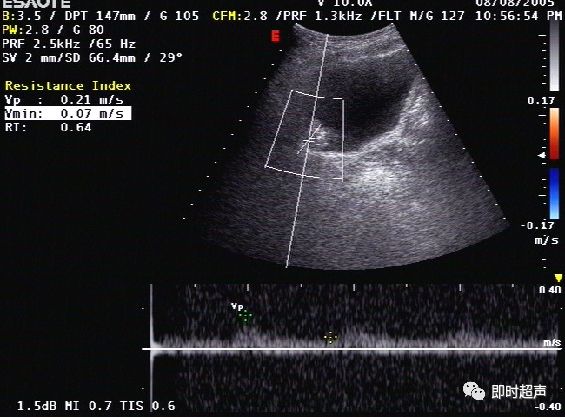

患者,男性,55岁,无痛肉眼血尿,临床实验室检查:尿常规:镜下血尿,超声声像图如下:

图1为二维声像图,肿瘤为稍强回声光团,呈不规则菜花样。

图2为彩色多普勒声像图,显示肿瘤内部可见细条状血流信号。

图3为彩色血流频谱图,显示肿瘤内部可见动脉频谱,RI=0.64。

诊断思路:

- 该患者为中年男性,为膀胱癌好发年龄

- 超声图像显示膀胱内可见一不规则菜花样团状中等回声

- CDFI:显示肿瘤基底部有细条状血流彩色Doppler频谱显示有动脉频谱:RI=0.64

- 综上所述,诊断应首先考虑膀胱恶性肿瘤

病理结果:

患者进行了肿块的切除,术后病理:膀胱移行上皮细胞腺癌